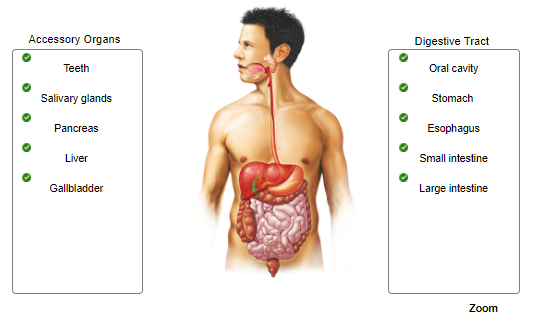

Label only the accessory organs of the digestive system.

Identify the roles of the asscessory organs and digestive tract